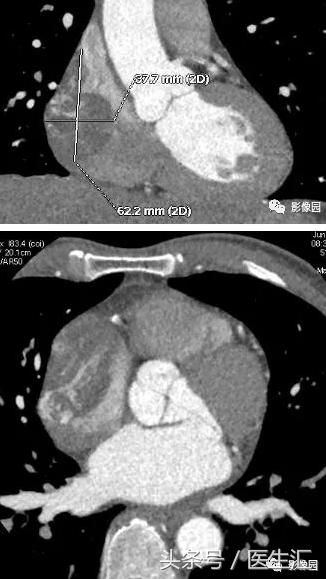

评论:右心房扩大,密度如常。增强扫描动脉期见欠规则结节状充盈缺损影,病变内见斑片状强化。

病理所见:右房扩大,右房内肿瘤约4x125px,附着于右房游离壁约2x75px,未累及房间隔及三尖瓣。

(右房占位)血管肉瘤,浸润心肌组织。